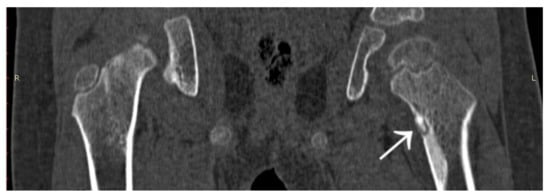

3.4. Case 4: OO Masking as a Fatigue Fracture